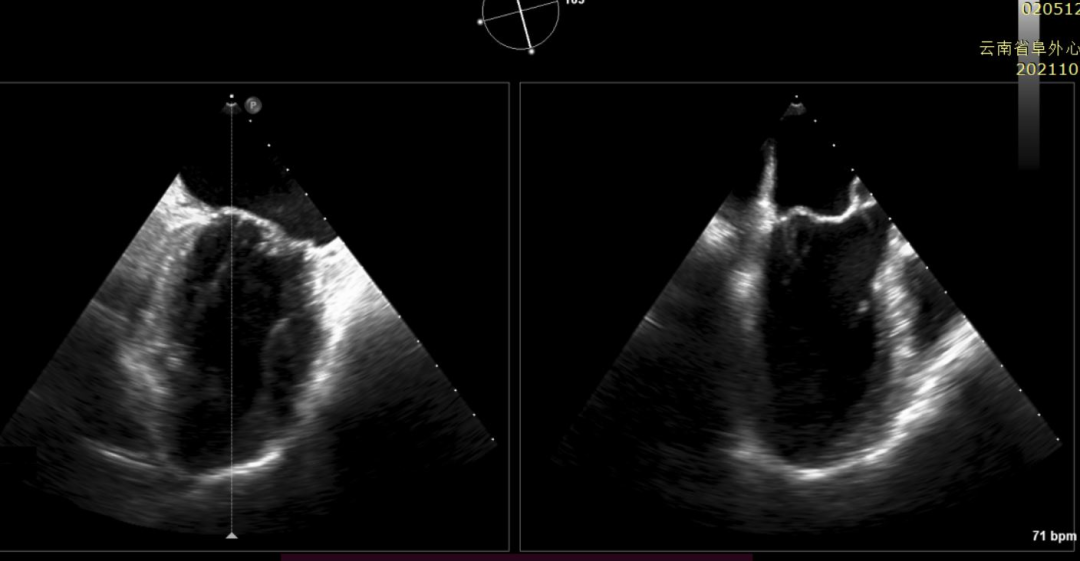

经过云南阜外医院结构性心脏病MDT团队综合讨论评估该患者病情后,患者为传统手术高危患者,瓣膜病变解剖无法行介入修复,决定进行MitraFix™经心尖二尖瓣植入。术前心脏CTA二尖瓣D形瓣环面积折算直径34mm, 模拟植入34号介入二尖瓣膜(外经约40mm)后左心室NeoLOVT面积可(>150mm2)。手术在单纯超声引导下完成,采用左侧肋间4cm微创切口心尖入路,在超声引导下,输送系统准确跨瓣,并将瓣膜准确释放于二尖瓣瓣瓣环,瓣膜释放后支架贴合牢固,无瓣周漏及瓣内反流,二尖瓣前向血流通畅,平均压力阶差2mmHg,左心室流出道通畅,流出到血流速度为2.3m/s,平均压力阶差8mmHg(图2-3,视频1)。顺利撤出输送系统,关闭心尖切口,手术顺利结束。

图2:术中TEE见左心增大,收缩期瓣叶广泛脱垂,心功能降低